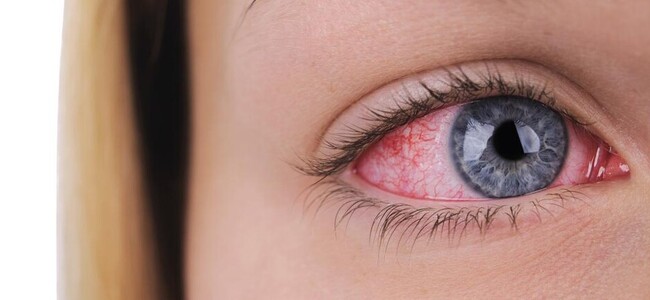

Контактна корекція в екстремальних умовах